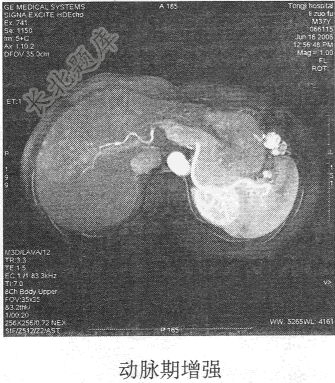

- 单项选择题患者男,54岁。体检发现肝脏占位,MR图像如下,最有可能的诊断是

C、肝血管瘤